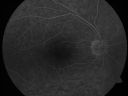

Sturge-Weber Encephalotigeminal Angiomatosis - Facial Hemangioma and Asymptomatic Ipsilateral Diffuse Choroidal Hemangioma752 views61-year-old man with Sturge-Weber syndrome with a hemangioma on the left side of his face.

VISUAL ACUITY: Vision OD is 20/50, PH 20/30; OS 20/80, PH 20/30. IOP: OD 16, OS 19.